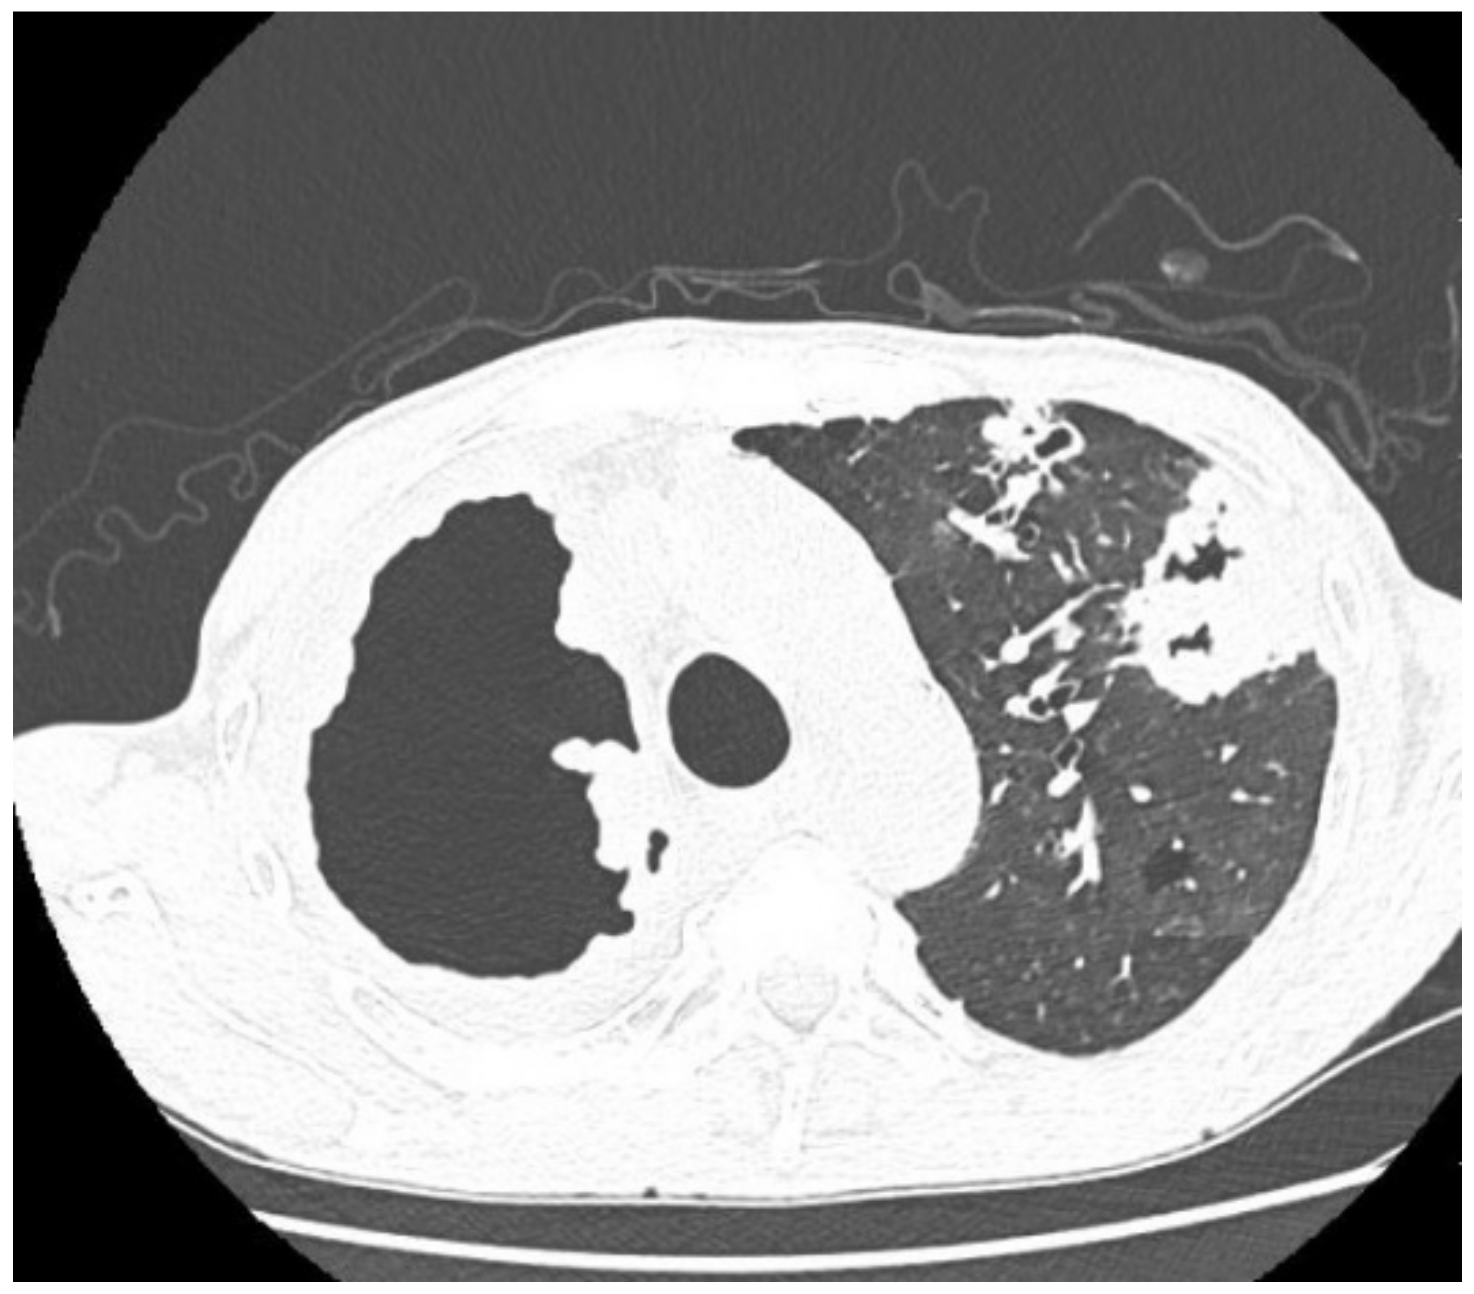

| Imaging studies during antimycobacterial treatment | Chest X-ray: After 2 mo of treatment—an irregular infiltration in the upper area of the right lung (Figure 2A). After 5 mo of treatment—reduced infiltration (Figure 2B) Chest CT: After 5 mo of treatment an oval nodular lesion with calcification, enlarged right and left mediastinal nodes, nodular lesions in the lungs (Figure 3A,B) | Chest X-ray: No improvement by radiographic criteria after 17 mo of treatment (Figure 5B). Still no improvement by radiographic criteria after further 2 years of treatment (Figure 5C) Chest CT: An extensive cavity in the upper lobe of the right lung, infiltrative lesions in the middle lobe, cavernous lesions in the left lung (Figure 4) |